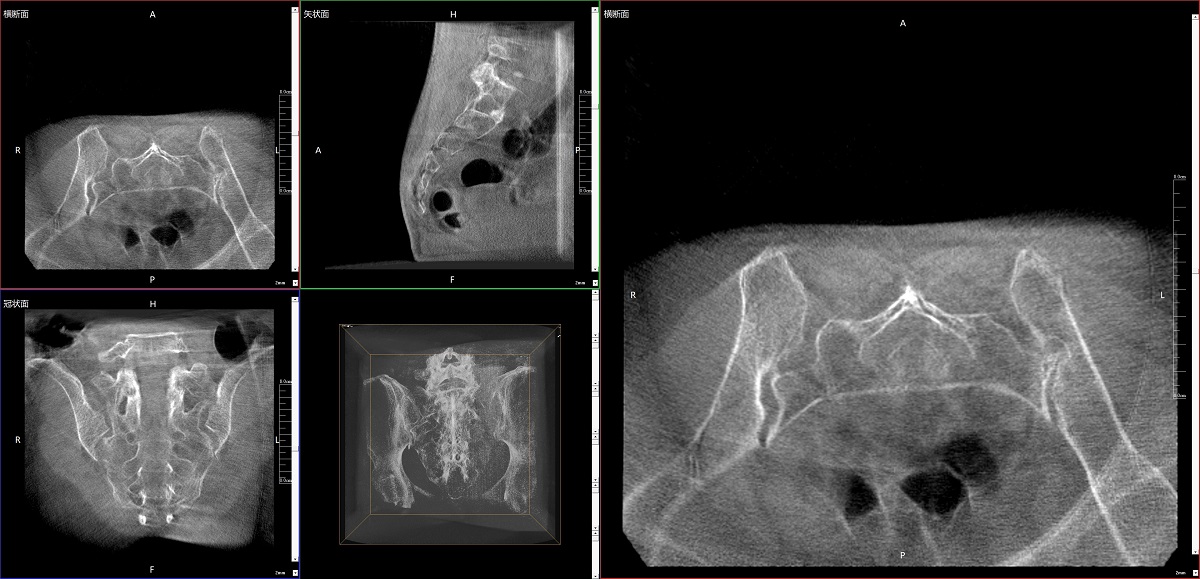

在骨科手術(shù)中,影像相當(dāng)于醫(yī)生的“眼睛”,要先“看得清",才能“算得準(zhǔn)” “打得穩(wěn)”。普愛(ài)醫(yī)療第三代平板三維C形臂協(xié)同醫(yī)院創(chuàng)傷導(dǎo)航機(jī)器人已開展多例“骨盆骨折微創(chuàng)手術(shù)”,成為上海市第七人民醫(yī)院手術(shù)技術(shù)創(chuàng)新的一大亮點(diǎn)。

普愛(ài)醫(yī)療第三代平板三維C形臂出色的二維透視和術(shù)中三維成像效果,為機(jī)器人提供了精確的術(shù)中影像依據(jù),協(xié)同提升手術(shù)整體的精準(zhǔn)度和效率,為患者帶來(lái)了更安全、更高效的醫(yī)療服務(wù)體驗(yàn)。